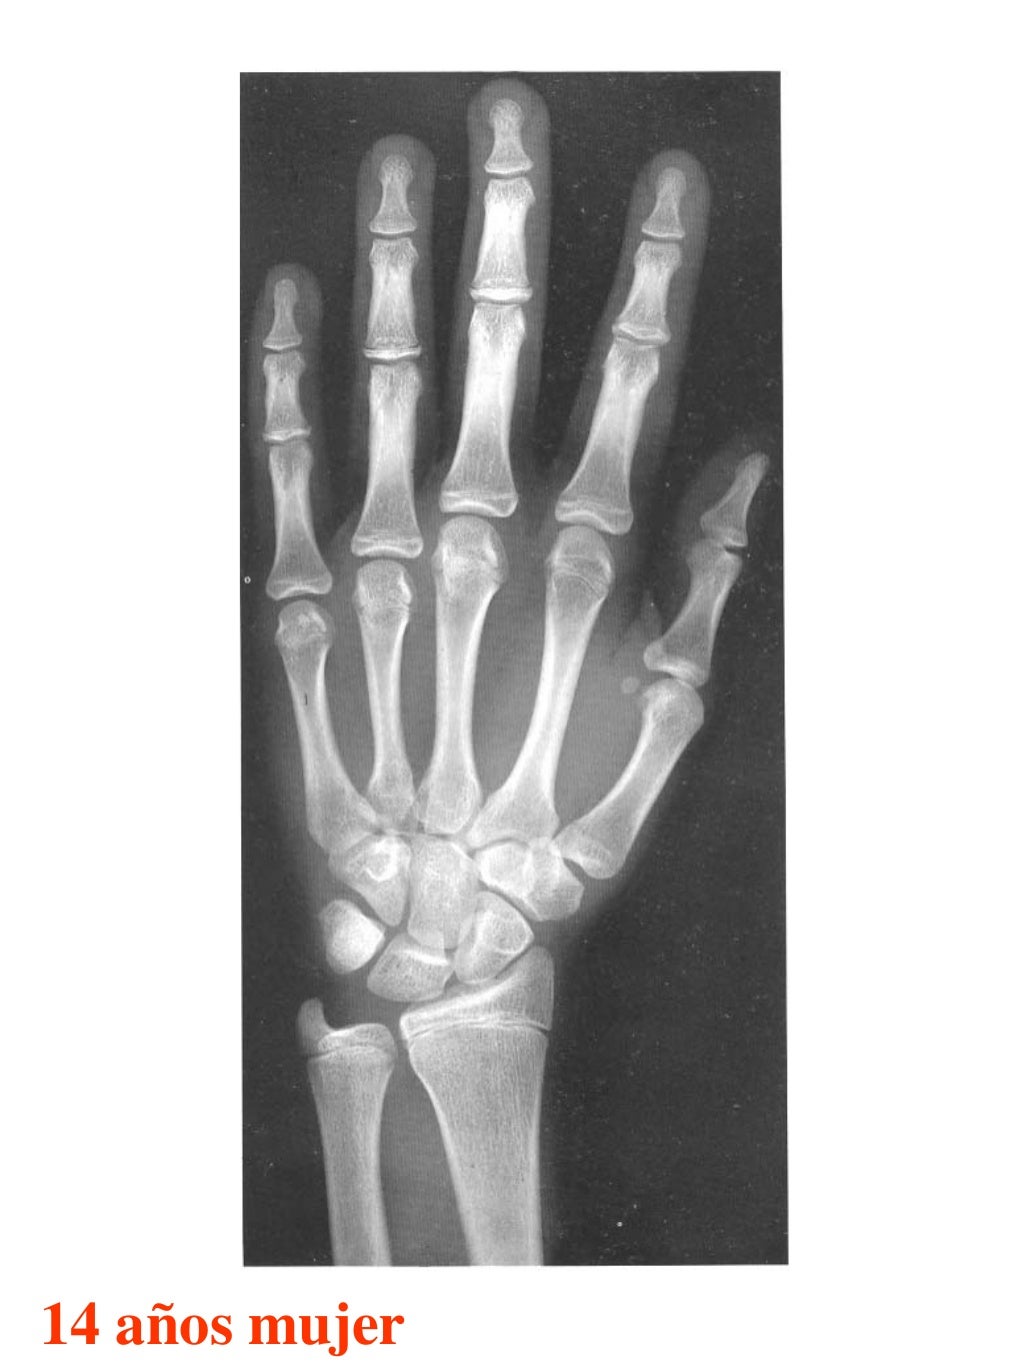

Figura 2 Imágenes de radiografías de mano y muñeca izquierda del

Figura 2 Imágenes de radiografías de mano y muñeca izquierda del Tablas De Greulich Y Pyle Edad Osea The greulich and pyle atlas is used to estimate the age of children and adolescents. El método de greulich y pyle(1) es un método simple de valoración de la edad ósea en pacientes pediátricos. El diagnóstico y la clasificación se basan en el examen físico, el análisis del crecimiento, la maduración ósea, la ecografía de útero y gónadas, y los. Tablas De Greulich Y Pyle Edad Osea.